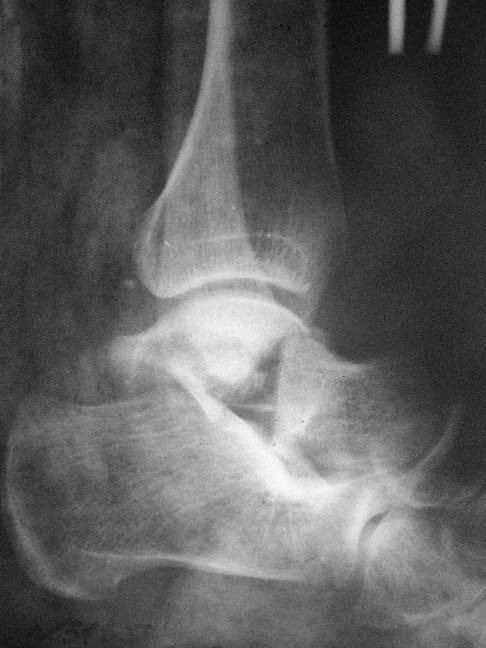

Из-за многооскольчатости дистальной части малоберцовой, где невозможно было провести фиксацию шурупами, перелом зафиксирован подпирающей пластиной, которая должна служить дополнением отсутствующей дистальной части малоберцовой (lateral cortex substitute).

Для стабильности два шурупа на синдесмоз.

Медиальную рану с приближенными краями продолжаем вакуумировать (KCI). Наружный фиксатор оставлен на пару недель, надеюсь, небольшая рана будет гранулировать и закроется без кожной пластики. Фиксация медиальной ложыжки не планируется.